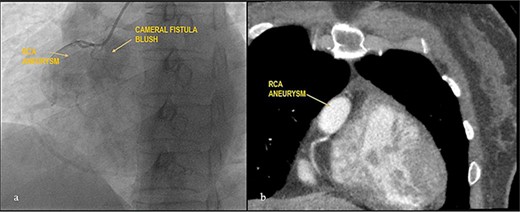

Case 2

Apparently healthy 44-year-female being evaluated as a potential donor for renal transplant, her echocardiography showed dilated right atrium and ventricle with moderate tricuspid regurgitation. Gated cardiac CT was done which revealed proximal RCA aneurysm measuring 2.1×2.4 cm and CAG which revealed RCA–right atrial (RA) cameral fistula. Heart arrested with antegrade cardioplegia after aorto-bicaval cannulation. RA fistula suture ligated through right atriotomy. The aneurysm excised, RCA mobilized and reimplanted into right sinus of valsalva (RSOV). On weaning off of bypass, severe RV dysfunction observed and cardiopulmonary bypass re-initiated. RCA bypass with reverse saphenous vein graft (RSVG) was done. Figures 2 and 3 show radiological and intraoperative images. She had a stormy postoperative course with multiple episodes of ventricular arrhythmias probably attributed to sacrifice of the infundibular and nodal branch, but was eventually discharged on 11th day after surgery.

Giant RCA aneurysm with CCF. (a) CAG showing RCA aneurysm with RA blush; (b) RCA aneurysm in cardiac CT.